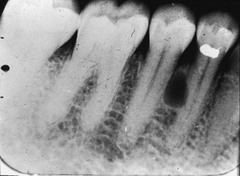

focal sclerosing osteomyelitis

-asymptomatic, bone adjacent to any tooth radiopaque area below roots -Mandibular 1st molar most common